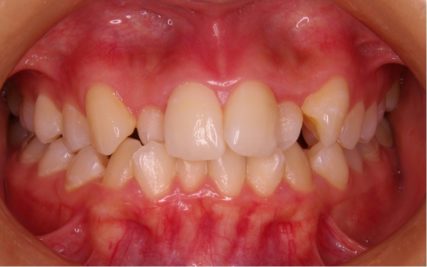

でこぼこ/20代女性

- 不正咬合/叢生(でこぼこ)

- 上下とも前歯のスペース不足が認められた。歯のサイズと顎の幅とのバランスが不調和な事が原因の1つとして考えられる。

- 上顎両側4番・上顎両側8番・下顎両側4番・下顎両側8番抜歯

- マルチブラケット装置(セルフライゲーションブラケット)/歯科矯正用アンカースクリュー

- 前歯部のでこぼこが解消され、正常咬合を獲得する事が出来た。又、歯科矯正用アンカースクリューを用いる事で抜歯スペースを有効に利用できた。